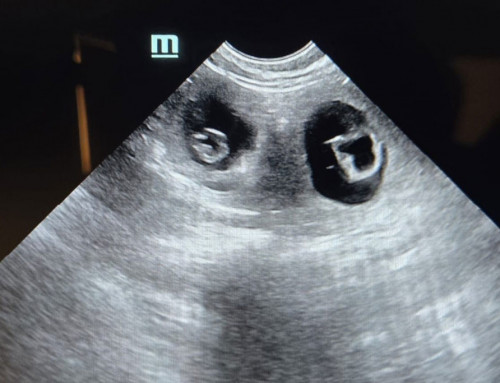

Elea hat bereits 4 kg zugenommen. So, wie es aussieht, wird das wieder ein größerer Wurf. Trotz allem rennt sie noch rum und ist guter Dinge :-)

Von Sabine Keßler|2026-03-02T16:45:51+00:00März 2nd, 2026|Zucht|Kommentare deaktiviert für Elea am 50. Tag der Trächtigkeit